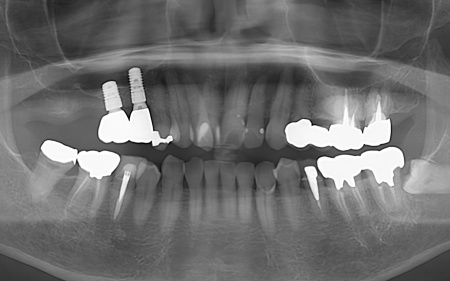

50代男性 バランスが崩れた噛み合わせをインプラント治療と被せ物治療で改善した症例

- 骨再生

- 詰め物・被せもの

- セラミック・ジルコニア

- インプラント

- サイナスリフト

- 治療期間の目安 3年

- 治療回数の目安 約45〜50回

約4,479,545円

【内訳】

サイナスリフト、骨移植、インプラント6本、他院インプラント人工歯作り替え、ジルコニアクラウン(インプラント人工歯6本、被せ物3本)、ダイレクトボンディング

治療のリスク

・外科手術のため、術後に痛みや腫れ、違和感を伴います ・メンテナンスを怠ったり、喫煙したりすると、お口の中に大きな悪影響を及ぼし、インプラント周囲炎等にかかる可能性があります ・糖尿病、肝硬変、心臓病などの持病をお持ちの場合、インプラント治療ができない可能性があります ・高血圧、貧血・不整脈な...